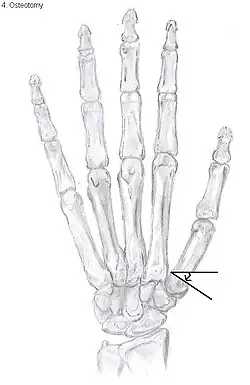

Metacarpal osteotomy

The aim of metacarpal osteotomy is to change the pressure distribution on the TMC joint. The hope is that this will slow the pace of development of osteoarthritis. There is no evidence that this procedure can modify the natural course of TMC OA. Osteotomy may be considered for people with mild arthritis.[24]

During osteotomy, the metacarpal is cut and a wedge shape bone fragment is removed to move the bone away from the hand.[35] Postoperative, the thumb of the patient is immobilized using a thumb-cast.

Possible complications are non-union of the bone, persistent pain related to unrecognized CMC or pantrapezial disease and radial sensory nerve injury.[24]